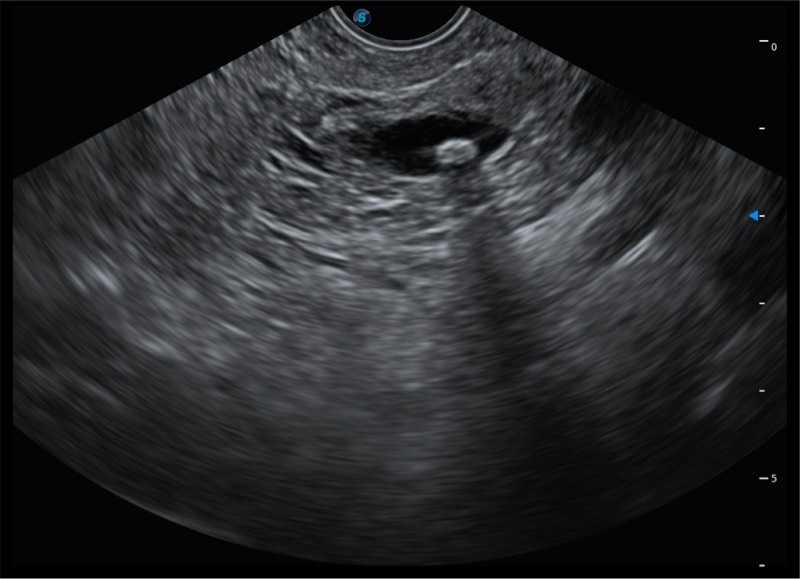

搭载百万级CMOS成像技术

及自主研发凸阵换能器,

可呈现优质的内镜和超声画面

基于二十年的超声技术积累,乐玩lewin国际提供了最新一代的独立超声主机,在提供高质量图像的同时满足多学科使用。具备常见多普勒技术并提供弹性成像、声学造影等高端影像技术。新一代传感器具有更强的抗干扰能力并减少图像伪影。

150°超声扫描角度